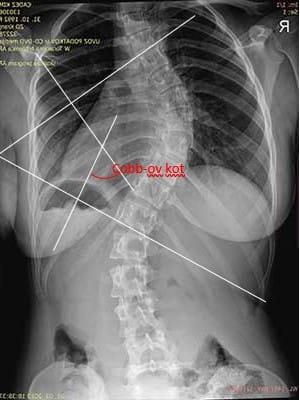

RENTGEN

Na rentgenskem posnetku merimo skolioze z meritvijo po Cobbu. Ta kljub temu, da ne opisuje 3D geometrije hrbtenice, še vedno velja za standardno klinično uporabno metodo. Pri določanju krivine najprej določimo zgornje in spodnje vretence, ki še pripadata tej ravnini. Nato potegnemo črti po zgornji ploskvi zgornjega in spodnji ploskvi spodnjega vretenca in pravokotnici na tej daljici. Ostri kot med tem dvema črtama imenujemo Cobbov kot (Persall, D. J., Reid, J. G. & Hedden, M. D. (1992). Comparison of Three Nonincasive Methods for Measuring Scoliosis. Ohys Ther, 72(9), 648–657).